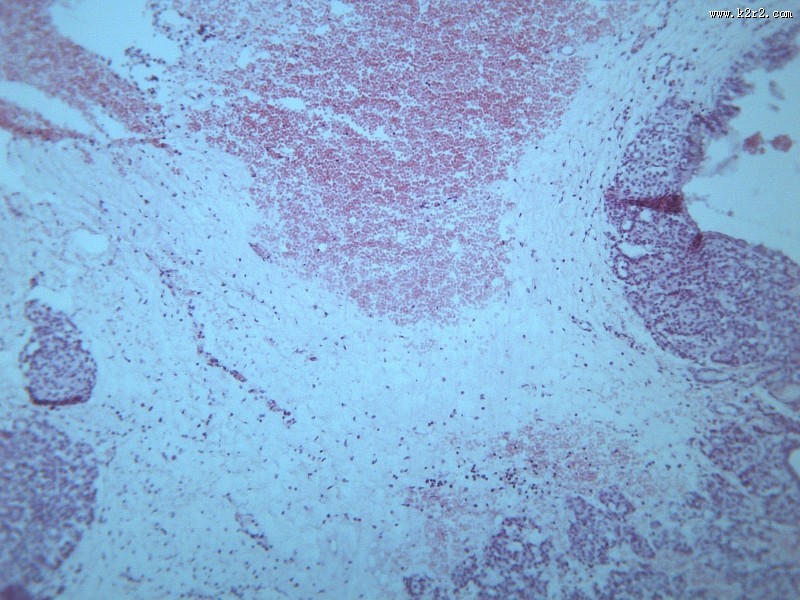

首页 > 其他类别 > 畸胎瘤(12张) > 畸胎瘤 第3张

畸胎瘤 - 第3张

第 3 / 12 张

猫扑风铃上传畸胎瘤 图集中 / 共有 12 张图片